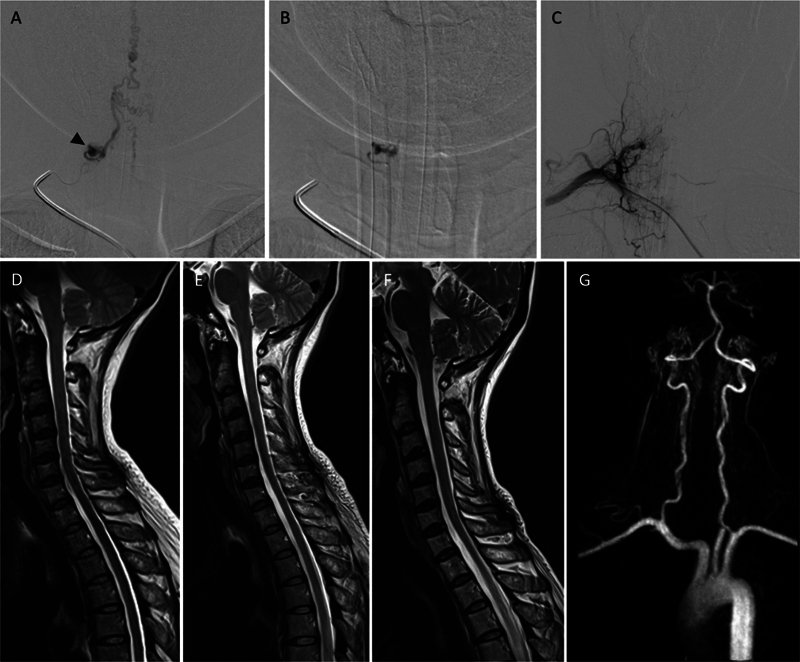

下颈动静脉瘘(AVFs)是一种罕见而复杂的血管畸形,由于其位置和表现多变,给临床带来了重大挑战。虽然上颈椎avf已被广泛研究,但下颈椎avf仍未得到充分研究。本研究旨在回顾下颈椎avf患者的临床表现、治疗策略和结果,以提高对治疗方法的认识和改进。我们对2006年6月至2023年12月期间在我院治疗的脊柱血管畸形患者进行了回顾性分析,确定了2例下颈椎avf。此外,采用Ovid MEDLINE、PubMed和Cochrane等数据库,按照系统评价和荟萃分析指南的首选报告项目,对44例下颈椎avf患者进行了系统文献综述。收集的数据包括患者人口统计学、临床表现、瘘管类型、动脉和静脉受累、治疗方式和神经预后。包括我们2例在内的44例下颈椎avf患者中,50%为女性,平均年龄48.68岁(范围4-76岁)。临床表现各不相同,27.3%出现出血,18.2%出现脊髓病,18.2%无症状。静脉引流方式在症状严重程度中起着重要作用,复杂的髓周静脉引流和逆行静脉引流会导致更差的结果。治疗方式包括血管内栓塞(40.9%)、手术切除(25%)和联合入路(18.2%),54.5%的病例恢复良好。下颈椎avf由于其不同的表现和复杂的血管解剖结构而面临多种临床挑战。早期诊断和量身定制的管理,包括血管内栓塞和手术切除,是优化患者预后的必要条件。需要进一步研究以更好地了解无症状房颤的自然史并改进治疗方案。

Lower cervical arteriovenous fistulas (AVFs) are rare and complex vascular malformations that pose significant clinical challenges due to their location and variable presentation. While upper cervical AVFs have been extensively studied, lower cervical AVFs remain underresearched. This study aims to review the clinical presentations, management strategies, and outcomes of patients with lower cervical AVFs to enhance understanding and improve treatment approaches. We conducted a retrospective analysis of patients with spinal vascular malformations treated at our institute between June 2006 and December 2023, identifying two cases of lower cervical AVFs. Additionally, a systematic literature review was performed following the Preferred Reporting Items for Systematic Reviews and Meta-Analyses guidelines, including 44 patients with lower cervical AVFs, using databases such as Ovid MEDLINE, PubMed, and Cochrane. Data collected included patient demographics, clinical presentation, fistula type, arterial and venous involvement, treatment modality, and neurological outcomes. Among the 44 patients with lower cervical AVFs, including our two cases, 50% were female, and the mean age was 48.68 years (range: 4-76 years). Clinical presentations varied, with 27.3% experiencing hemorrhage, 18.2% presenting with myelopathy, and 18.2% remaining asymptomatic. Venous drainage patterns played a significant role in symptom severity, with complex perimedullary and retrograde venous drainage contributing to worse outcomes. Treatment included endovascular embolization (40.9%), surgical resection (25%), and combined approaches (18.2%), with good recovery achieved in 54.5% of cases. Lower cervical AVFs present diverse clinical challenges due to their variable presentations and complex vascular anatomy. Early diagnosis and tailored management, including endovascular embolization and surgical resection, are essential for optimizing patient outcomes. Further research is needed to better understand the natural history of asymptomatic AVFs and improve treatment protocols.